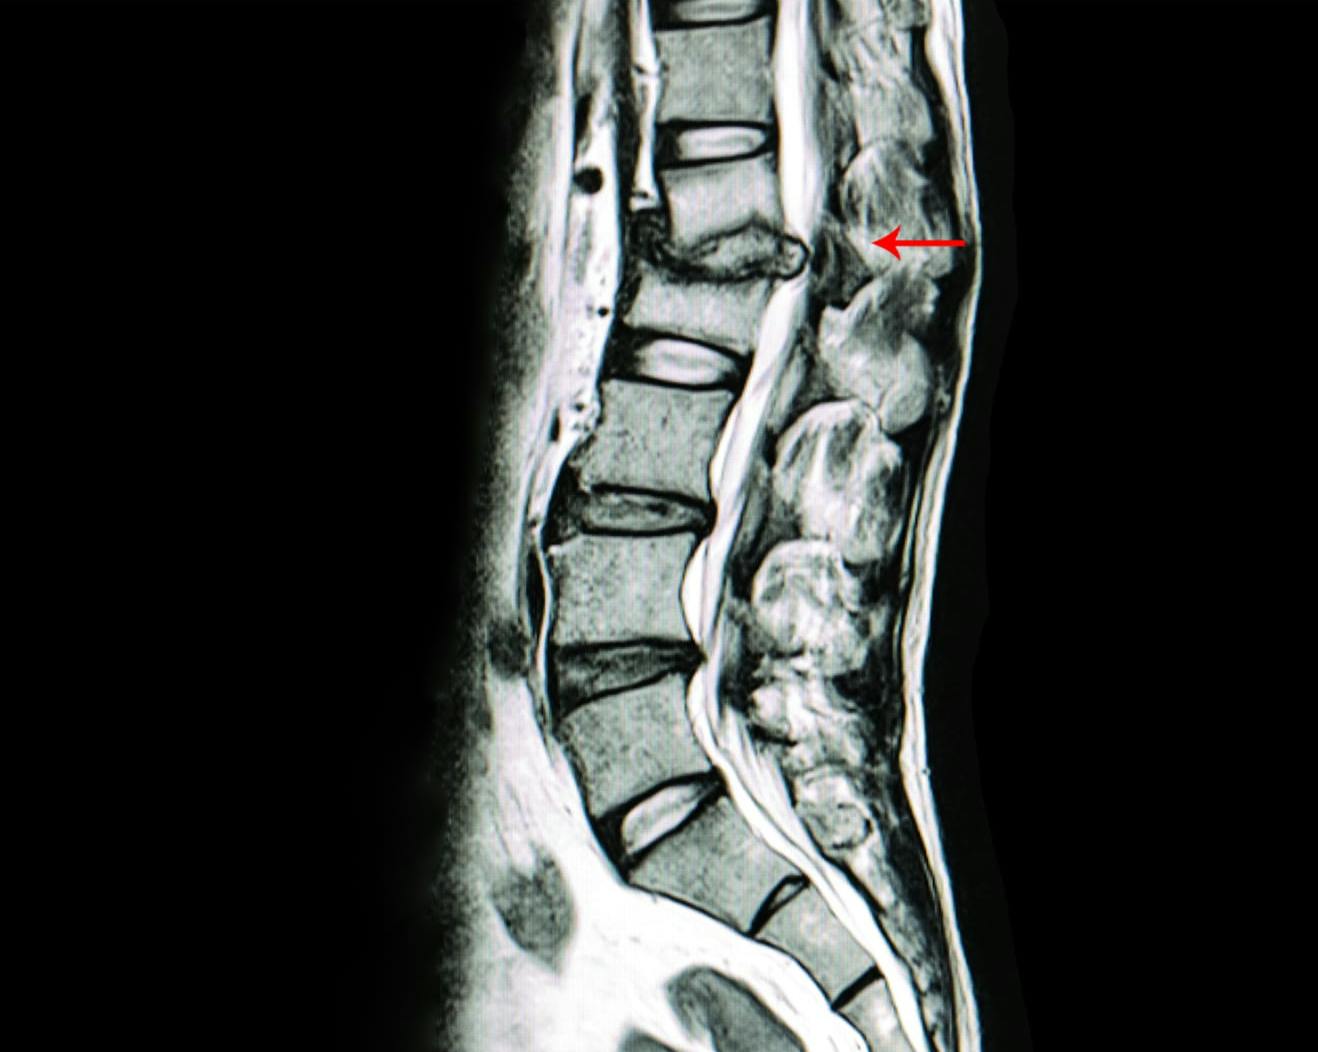

How is spinal stenosis diagnosed?

It involves a physical exam, review of medical history, and imaging tests like X-rays, CT scans, or MRIs.